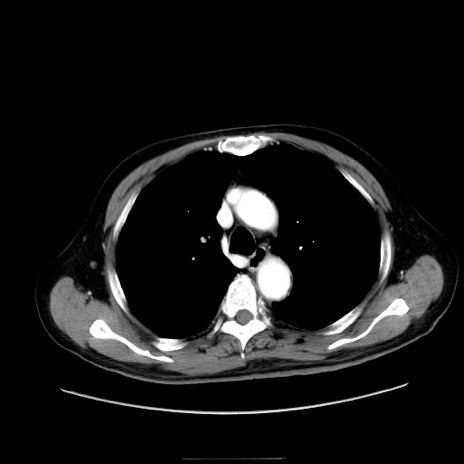

症例30(横断像)

冠状断像

【症例】80歳代男性

【現病歴】約6時間前から臍下部痛が出現。次第に腹部膨隆・背部痛も生じてきたため来院。背部痛の場所は変化しない。

【身体所見】意識清明、BT 36.3℃、BP  131/87mmHg、P 87bpm、SpO2 100%(RA)、臍周囲自発痛・圧痛あり、反跳痛なし、自発痛部位に一致して板状硬あり、腹部膨隆、腸雑音減弱、CVA tenderness両側陰性。